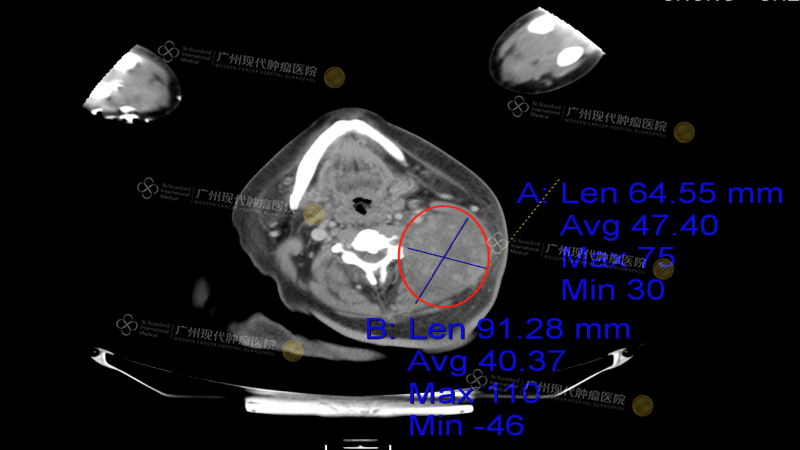

CHONG CHEE WEI, a 46-year-old man from Malaysia, first visited a local hospital in October 2023 due to persistent left-sided headaches. What he initially dismissed as routine fatigue turned into a life-altering diagnosis: nasopharyngeal malignant tumor with bilateral cervical lymph node metastasis, the largest lesion measuring 7.5 cm in diameter.

Accompanied by his brother, he entered Modern Cancer Hospital Guangzhou for the first time in April 2024. PET-CT results showed that there was still a huge active tumor residue (6.0*7.5*7.1cm) on the left side of his neck, and his condition was serious. The MDT of Modern Cancer Hospital Guangzhou quickly developed an individualized treatment plan for him, combining interventional therapy, targeted therapy and particle implantation therapy to precisely target the tumor. Interventional therapy is a minimally invasive treatment method that uses a very fine catheter to accurately inject high-concentration anticancer drugs into the tumor blood supply artery, which not only concentrates the drug effect, but also significantly reduces the toxic side effects of traditional chemotherapy on the whole body. Particle implantation therapy is to implant radioactive particles into the tumor through a fine needle, forming a kind of "in vivo targeted radiotherapy" that can kill cancer cells 24 hours a day with minimal damage to surrounding normal tissues.

CHONG CHEE WEI received four interventional treatments and one particle implantation in the hospital. The entire treatment process was almost painless, and the postoperative recovery was good. It is gratifying that within two or three days after the first interventional treatment, his mental state showed significant improvement, and his appetite and physical strength were significantly improved. As the treatment continued to advance, after the third interventional treatment combined with particle implantation, the tumor volume was significantly reduced, and no discomfort symptoms appeared. In particular, in the follow-up examination two months after the fourth interventional treatment, the examination results showed that the tumor had shrunk by two-thirds, and the cancer cell index had also dropped to a safe range. This series of positive treatment results made CHONG CHEE WEI and his brother very excited. They truly felt that life had been rekindled with hope, as if they had returned to the world from the brink of death.